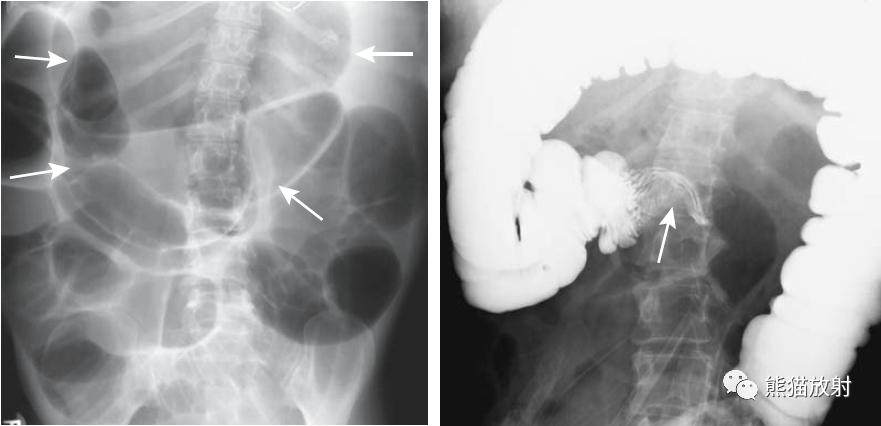

结-结肠肠套叠,由盲肠癌所致。钡灌肠显示横结肠中的肠套叠(箭头),在进一步的压力下,肠套叠移位至升结肠。

回-结肠套叠。CT定位像示7岁患儿的肠套叠(箭头)。Burkitt淋巴瘤所致。右图:10个月大的婴儿,疼痛和右上腹肿块。X线平片示横结肠(箭头)区域有软组织肿块。钡灌肠证实为肠套叠。